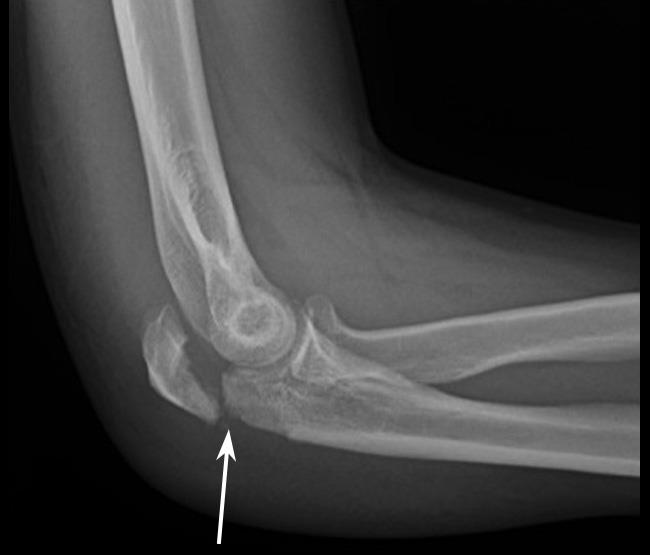

The most reported symptom is pain located on the outside of the elbow either on the bony part itself (the lateral epicondyle) or on the extensor muscles. Pain can radiate upwards along the upper arm and also downwards in and around the forearm. There may also be a weakness and / or pain when gripping items day to day little kettles etc.

- Pain over the outer park of the elbow and / or 1-2cm below